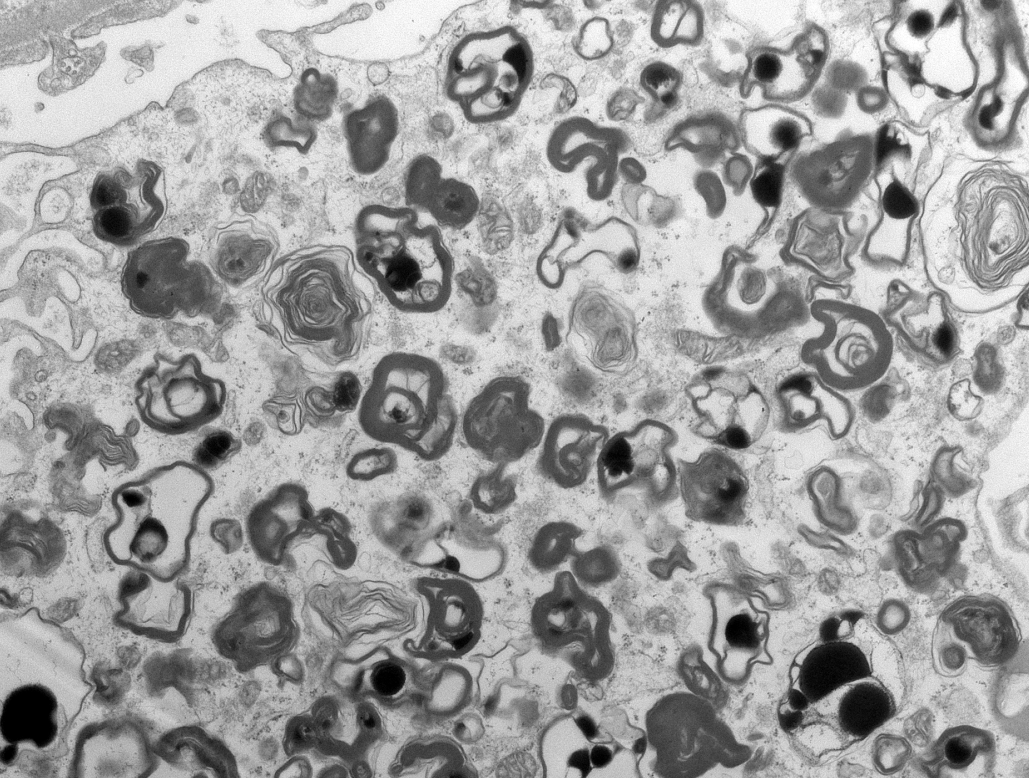

Mini case-series of crystal-storing histiocytosis (CSH) affecting predominantly glomerular loops with detailed literature review of renal CSH, images of one of the cases are depicted below, authors.elsevier.com/c/1Zh4S3uV~y8B…